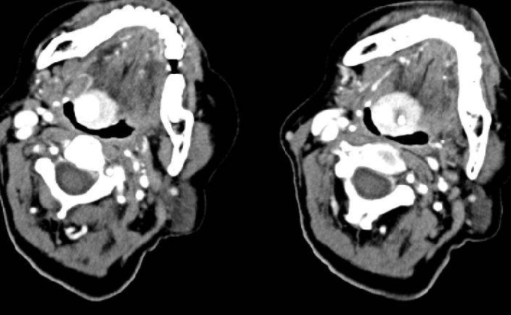

甲状舌管囊肿是颈部常见的先天性囊肿,是由甲状舌管残留上皮形成的囊肿。典型表现为颈中线甲状舌膜水平肿块,靠近舌骨。发病部位多位于舌骨中线、舌骨上方或舌骨略下方。在显微镜下,粘液腺和甲状腺滤泡常见于囊肿内衬假复层纤毛(呼吸道上皮)或鳞状上皮。

哈哈,我不会告诉大多数人。这是医生的绝活。我听说他们可以做各种设备(检查)、超声波、CT和MRI...我最喜欢做超声波检查。